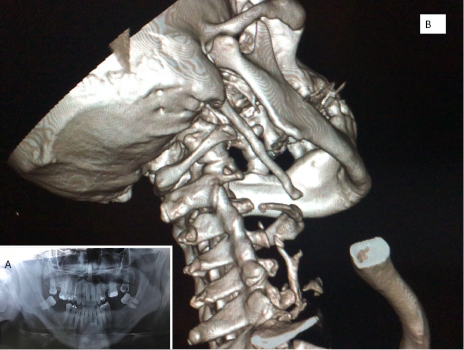

Paciente masculino de 48 años que fue tratado por síndrome de articulación temporomandibular por más de 2 años sin respuesta al tratamiento. Consulta al Servicio de Cirugía donde manifiesta intenso dolor a predominio izquierdo. Detalla cervicalgia, odinofagia, disfagia, otalgia y disminución de la apertura bucal. Solicitamos estudios de rutina y radiografía panorámica (foto 1/A); y con TAC con reconstrucción 3 D fue posible observar que las apófisis se extendían hasta el hioides con una longitud de más de 8 cm (foto 1/B).

Se programó una cirugía por vía externa realizando bajo anestesia general con intubación orotraqueal una incisión subangulomandibular con extensión sub mastoidea (foto 2/A). Se individualizó y resecó la apófisis estiloides izquierda sin morbilidad por el procedimiento efectuado (foto 1/B). La longitud de la apófisis resecada, superaba los 4 cm (foto 2/C). Se externó a las 24 horas post operatorias sin complicaciones.